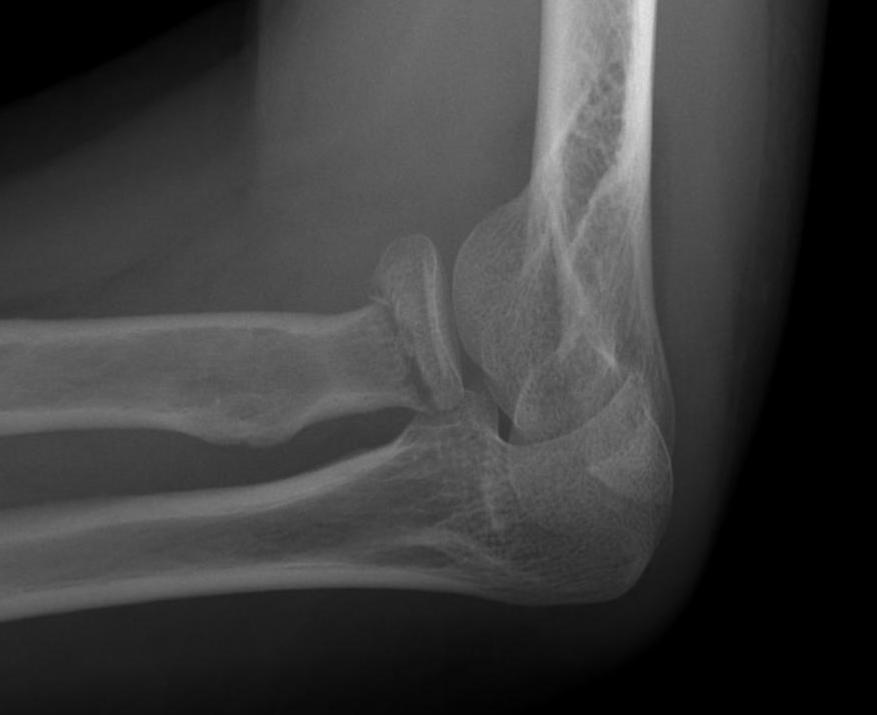

Type 3: Severely comminuted fracture / Non reconstructable

Type 3 radial head fractures

Type 4: Radial head fracture with elbow dislocation

Type 4 radial head fractures